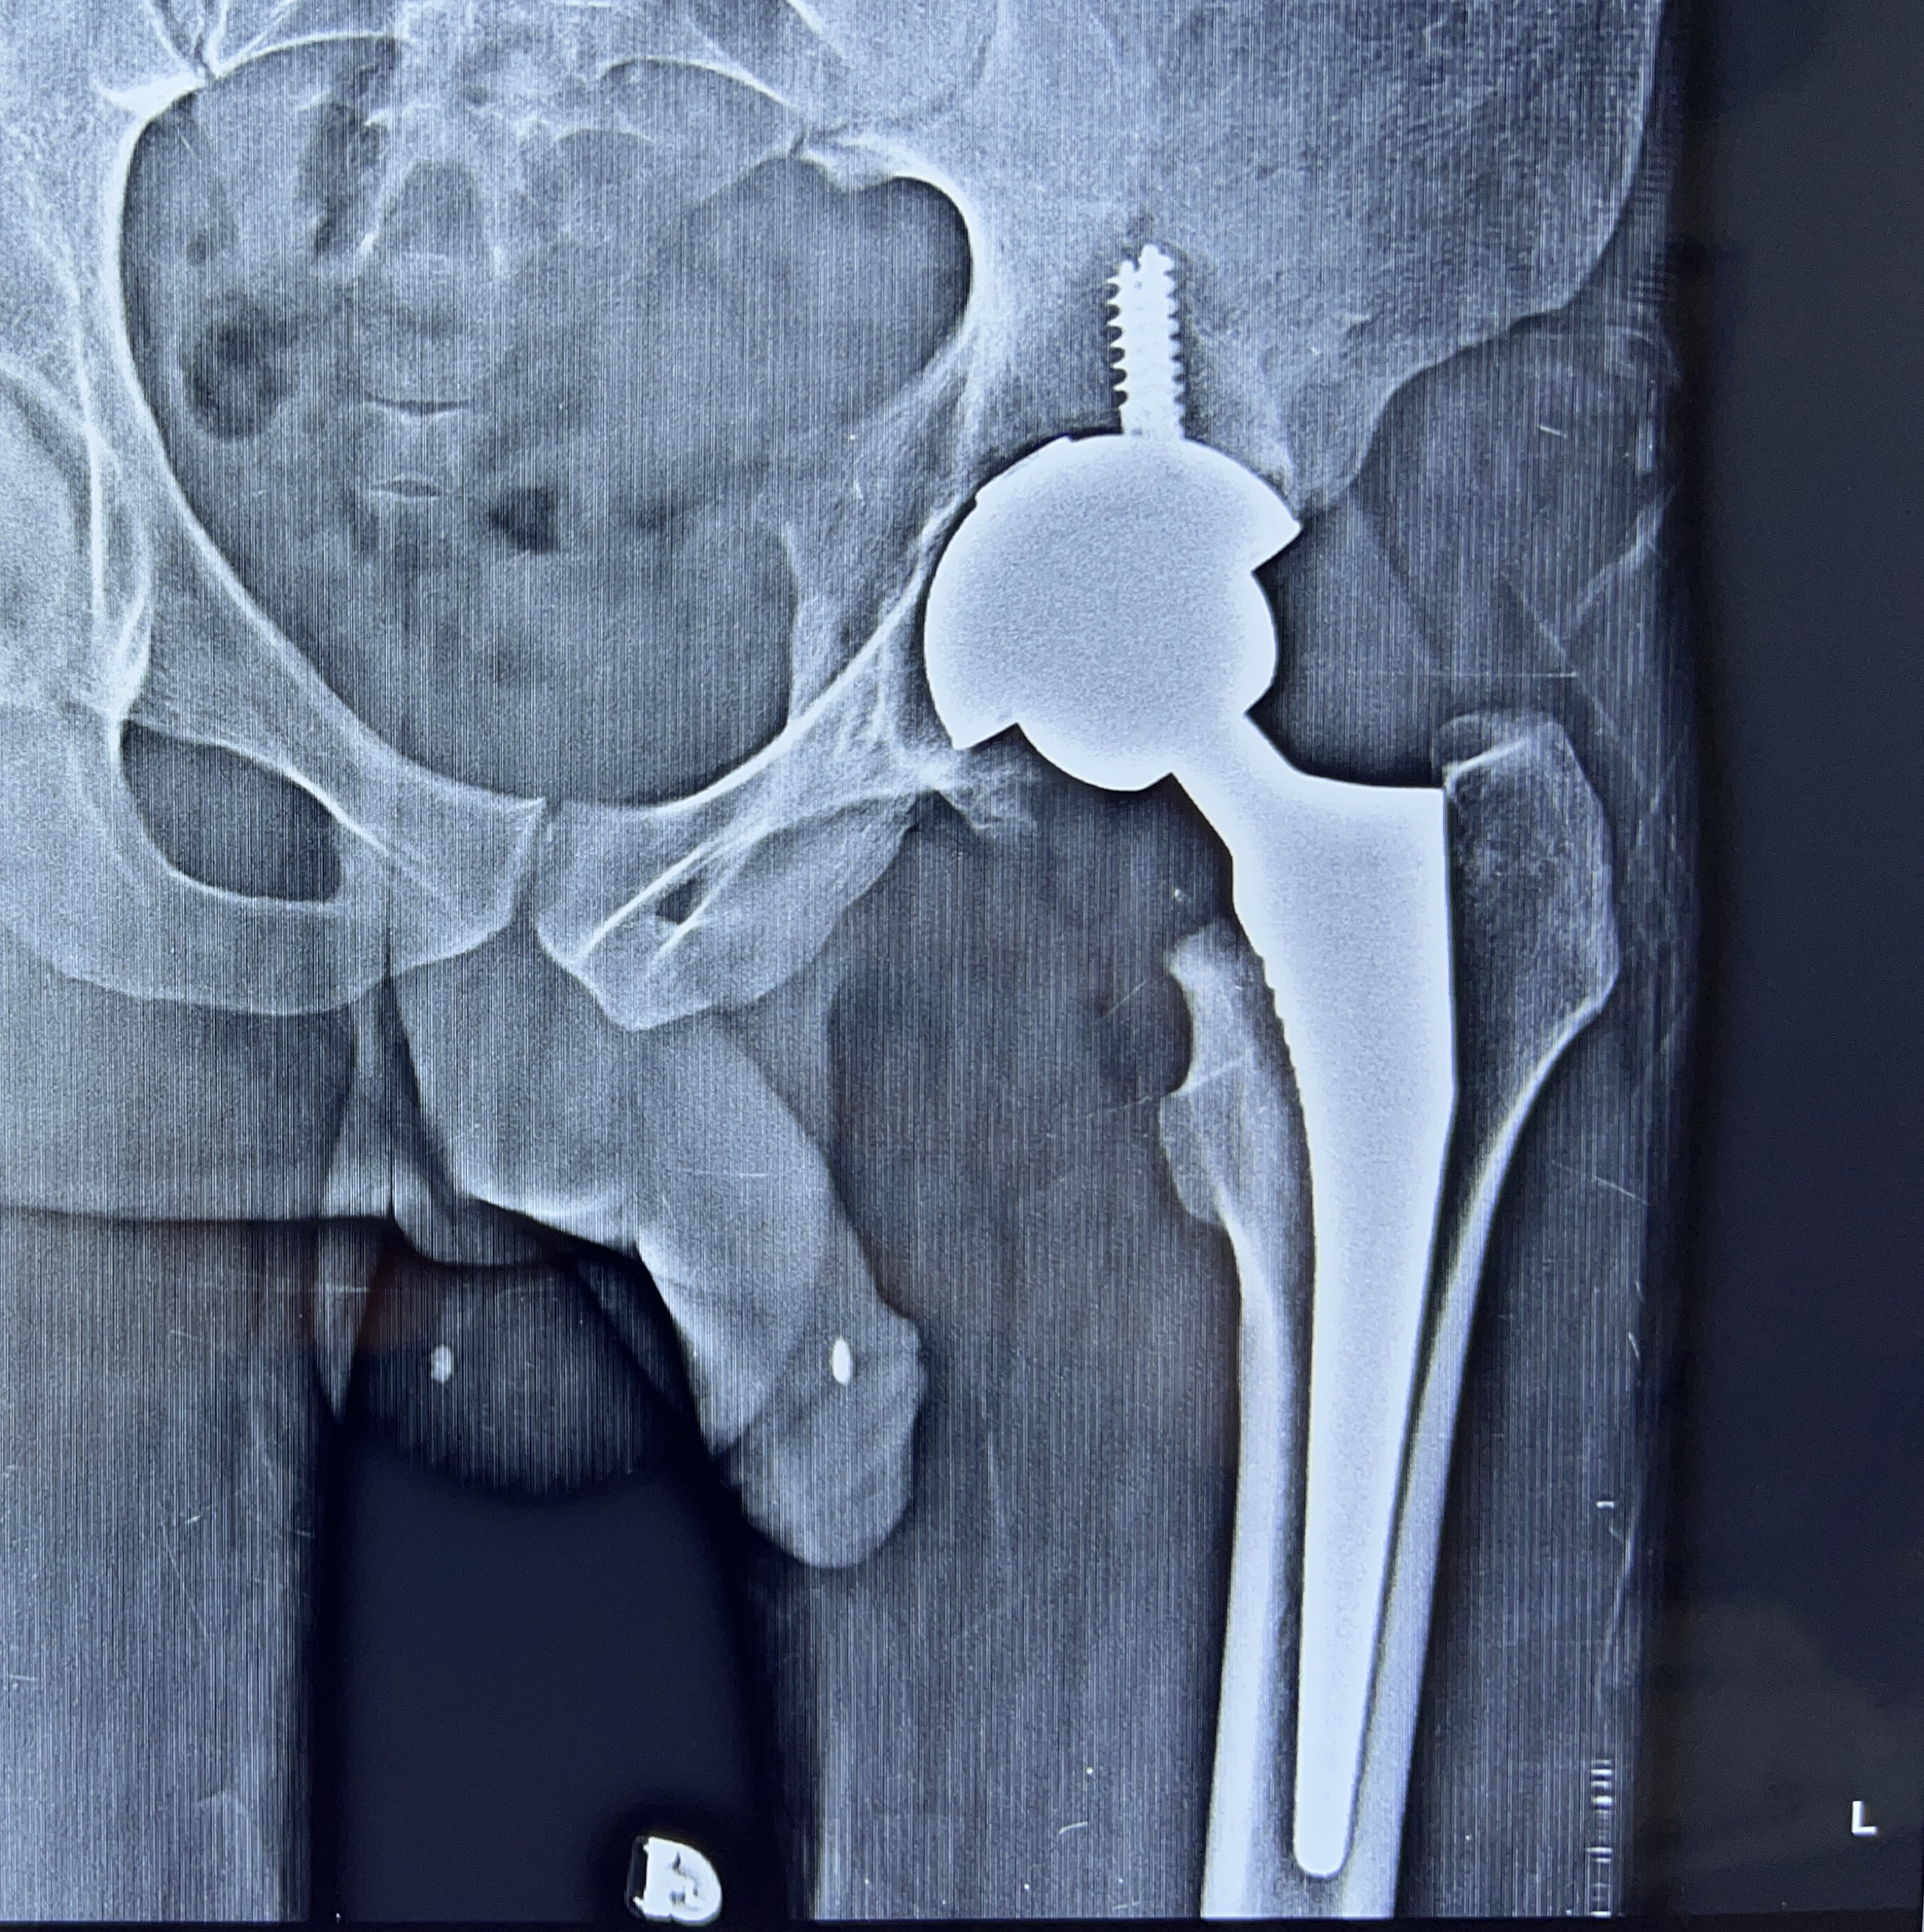

Total Hip replacement surgery is a surgery in which the worn out or damaged surface of the hip joint is replaced with prosthetic artificial surface made up of special metals like ceramic, chromium-cobalt, oxinium, titanium or polyethylene. The aim of this surgical procedure is to relieve you of your pain, deformity and swelling. So that you can get back to your active life. Now, that you have been suggested surgery, we help you plan and go for it.

Robotic hip replacement surgery is performed by the surgeon with the help of the robot. The surgeon will open up the hip, make a real time map of the deformed/ damaged surface ends of the bones and then using the robot, plan the surgery. Once the surgery is virtually performed on the robotic screen, the robotic burrs are used to burr off/ shave off the surface and tissue balance is achieved throughout the range of movement, an artificial implant is fitted on the surface. The wound is closed and dressing applied. You are then shifted to the recovery room!

Usually after discharge we call you after 8 days. If you have asked for a home dressing, we will help you with that and then your visit will be after one month from date of surgery, where we will HOPE to see you walk into the doctor’s office for an Xray and physical check of the hip. Fix up an appointment before coming for next visit.